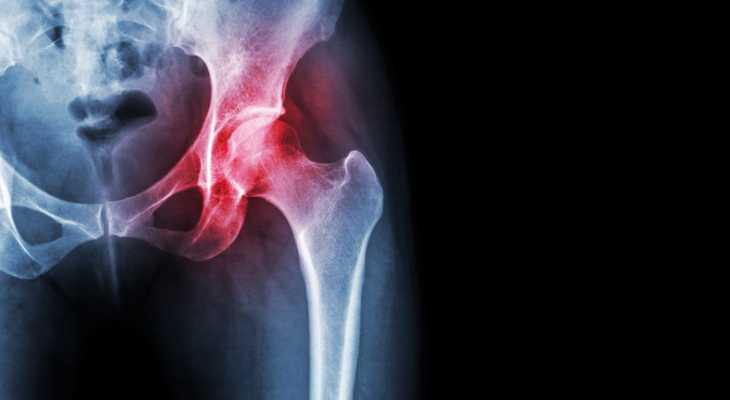

Osteoarthritis not only causes pain, but also makes it difficult to do a variety of everyday things. When your joints are stiff and achy, climbing stairs, buttoning your shirt, or getting in and out of the bathtub without falling become more challenging than you could ever have imagined. Adding chiropractic care to your osteoarthritis treatment plan can reduce both pain and stiffness.

- Keep Pain Under Control. Osteoarthritis happens when the cartilage at the ends of the bones in a joint wears away. Without that protective cushioning, the bones grind together every time you move the joint, causing jolts of pain. Chiropractic adjustments realign your joints and reduce painful pressure on the bones and cartilage. Self-reported pain levels in patients who had osteoarthritis of the neck decreased from 8.6 to 2.6 after receiving manipulation (adjustments) and mechanical mobilization device therapy, according to a research study published in the Journal of Manipulative and Physiological Therapeutics.

- Decrease Inflammation. Joint inflammation, a key factor in both pain and stiffness, is more likely to occur when your joints are misaligned. When misalignments are corrected, inflammation improves.